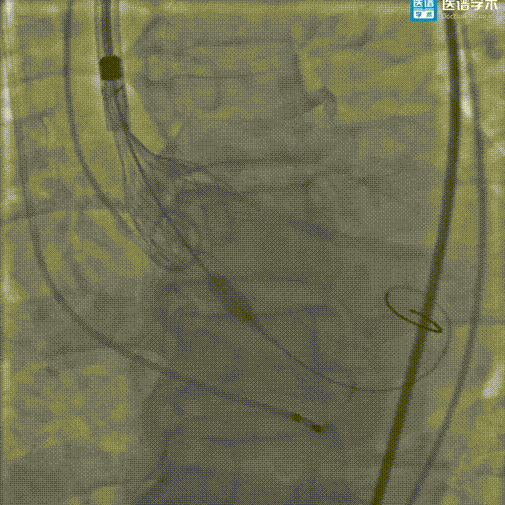

手术影像记录:

主动脉根部造影

导丝跨瓣

22mm球囊预扩

输送器顺利过弓

瓣环零位定位瓣膜

瓣膜释放到工作位

工作位造影评估

完全释放瓣膜

完全释放瓣膜后造影评估